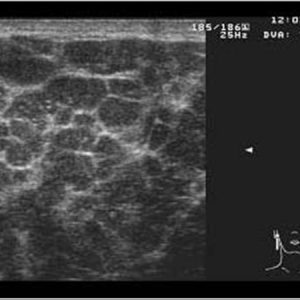

Bệnh Sjögren

Lượt xem: 201» 16-01-2021 -

Bệnh Sjögren

Lượt xem: 152» 16-01-2021 -

Bệnh Sjögren

Lượt xem: 162» 16-01-2021 -

Bệnh Sjögren

Lượt xem: 163» 16-01-2021 -